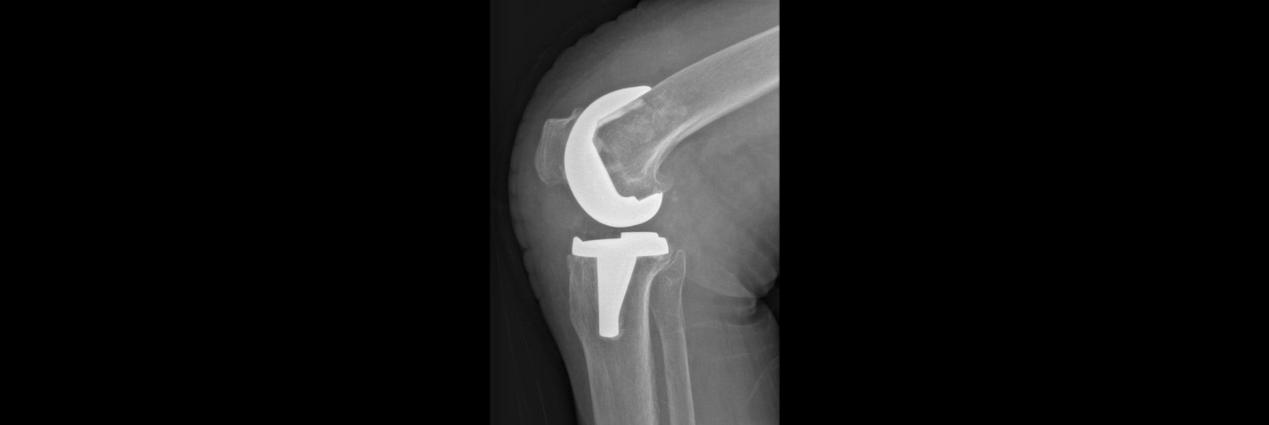

术前

66岁的孙女士,因右膝疼痛3年,加重2年于2月17日入院,患者曾接受关节腔玻璃酸钠等保守治疗,短期效果可,近期效果不明显,膝关节疼痛严重,每走一步都扎心的疼。入院后,董孟政副主任、黄贵云副主任一齐查看患者情况,经拍片检查诊断为膝关节骨性关节炎严重,定于2月19日为患者行关节置换术。

术后

术中,见患者膝关节软骨磨损严重,更换全膝关节假体。术后指导功能锻炼,术后第1天患者便可下地活动,术后3天已无需助行器自行活动,膝关节疼痛明显减轻,患者对手术效果非常满意,现已顺利出院。